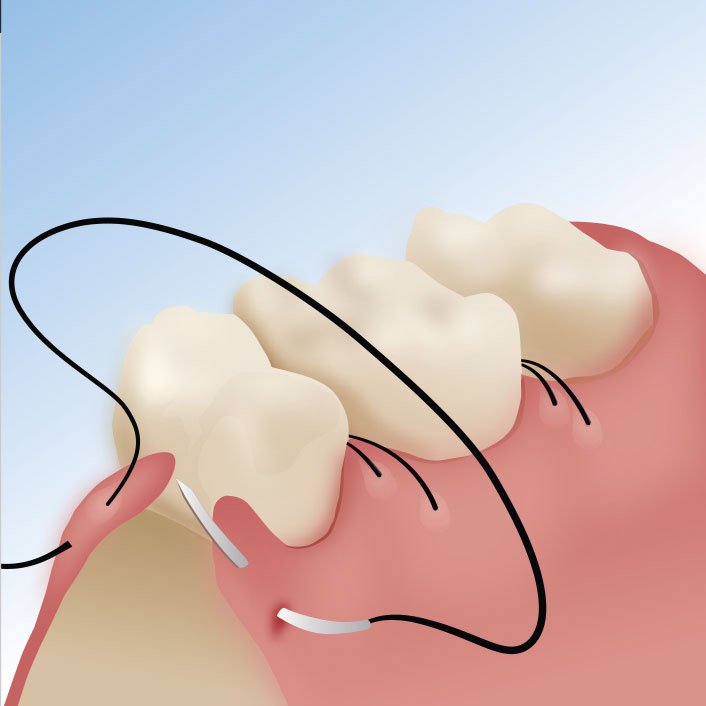

Flap Surgery

Flap surgery involves transporting healthy, live tissue from one location of the body to another – often to areas that have lost skin, fat, muscle movement, and/or skeletal support. There are several different types of flap surgery methods that may be utilized, depending upon the location of the flap and the structures that need to be repaired. The types include the following:

- Local flap

- Bone/soft tissue flap

- Musculocutaneous flap (muscle and skin flap)

- Microvascular free flap